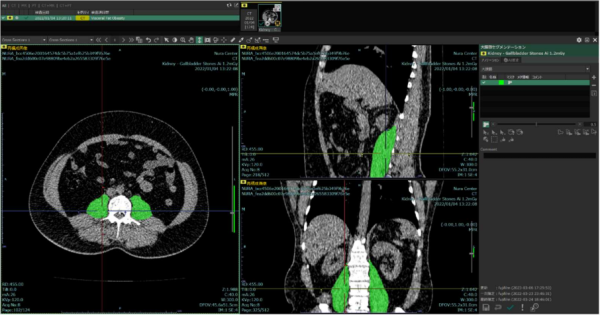

(2)「3D アノテーションツール」と「プロジェクト管理ツール」で画像診断支援 AI の効率的な研究開発を支援

・ 医用画像を AI に学習させるために行うアノテーションを 3 次元領域で効率的に行えるツール「3D アノテーションツール」を搭載。セグメンテーション※4、ディテクション※5、クラシフィケーション※6 など、学習データ作成に必要なマーキングやラベル付けを直感的な操作で付与できる。

※3 AI に学習させる学習データを作成するため、画像内にマーキングやラベル付けを行う作業。

※4 医用画像内から、特定の臓器や病変などの関心領域を輪郭抽出する機能を指す。